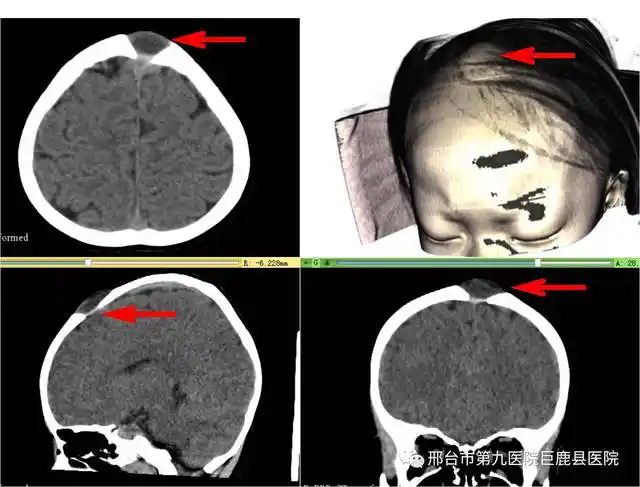

利用3d slicer导入头颅ct,vr重建头颅模型可见头发下隆起的头皮肿物